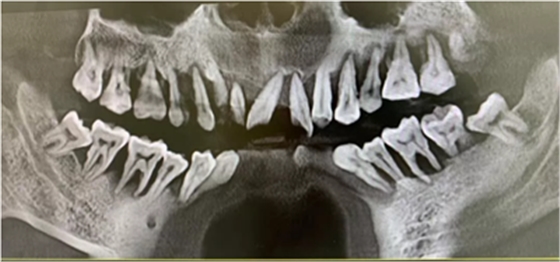

這是一個三十多歲的小伙子牙周炎的最終歸宿——全口牙松動,拔除。在口腔大夫那里,這些病例已經(jīng)司空見慣了,一句話形容:看起來,他們一顆牙也不缺,其實,已經(jīng)一顆牙也不在了!

正因為如此,牙周炎才被醫(yī)學界定論為繼癌癥、心腦血管疾病之后,威脅人類健康的第三大殺手,也是口腔健康的“頭號殺手”。最關(guān)鍵的是,每一個人都有可能遇上。